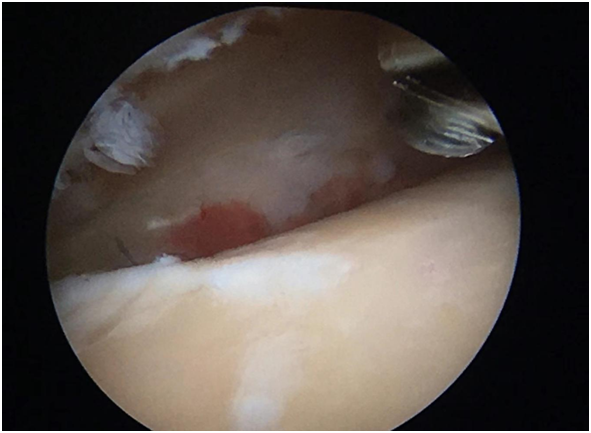

術(shù)中清晰的視野